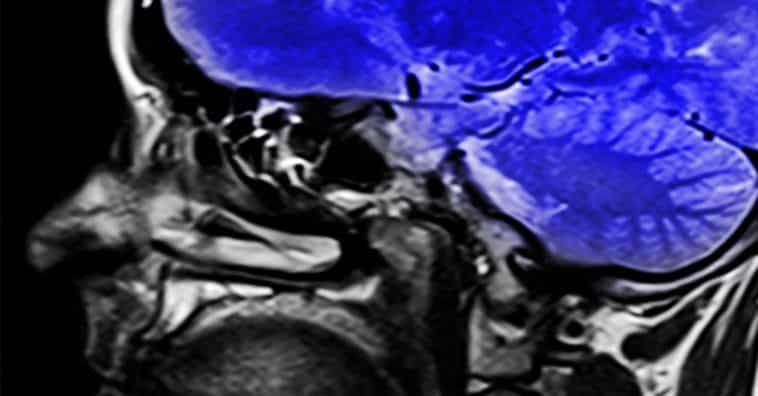

As doenças degenerativas do sistema nervoso estão entre as mais complicadas, pois afetam diretamente as capacidades motoras, de compreensão e até mesmo emocional. Os exemplos mais conhecidos são o Alzheimer e o Parkinson.

A doença de Huntington é uma doença degenerativa de caráter genético e é causada pela mutação de um único gene. A partir deste gene mutante, inicia-se um processo de produção da proteína huntingtina que é altamente nociva para o sistema nervoso. Este gene transmite uma ‘mensagem’ e aumenta a produção dessa proteína que afeta capacidades de fala, aprendizado e emocional.